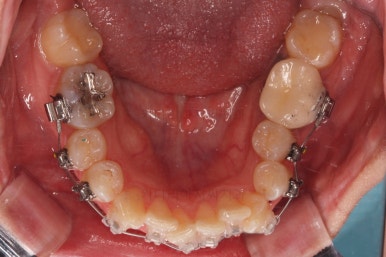

동래교정치과 마무리 사진입니다.

종료 이후에는 어금니의 기존 크라운 보철이 오래되고 탈이나서 재보철을 해주었습니다.

앞니는 비뚠채로 장기간 마모가 되어온 터라 형태가 부적절하긴 한데요.

보철로 마무리하기 보다는 최대한 자연스럽게 시리지 않는 선에서 다듬어 드리고 마무리를 했습니다.